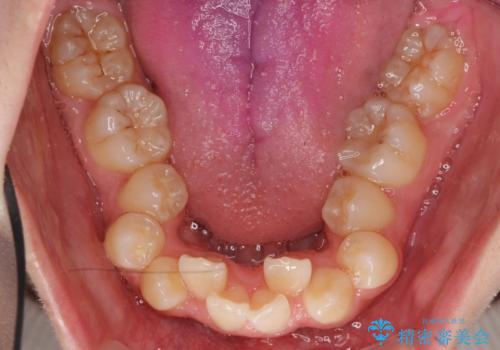

- 前歯のすき間と受け口を気にして来院。

下の前歯を後方に移動するため、ゴムを上下のマウスピースにかけてもらいました。